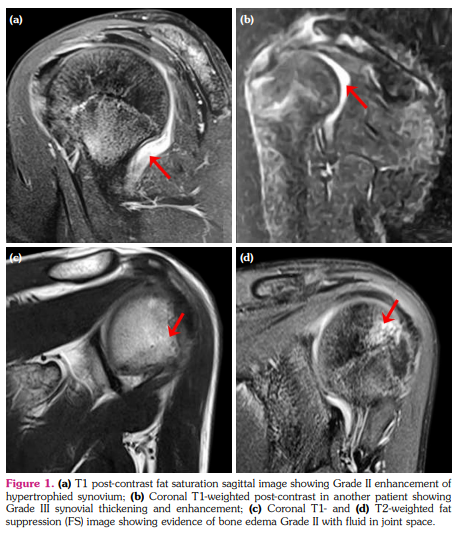

a) Synovial hypertrophy score: Thirteen (40.6%) joints in nine patients revealed synovial hypertrophy with a mean grade score of 0.7±0.9 (Figure 1 a, b). Five joints had Grade I and eight joints had Grade II synovial hypertrophy (Figure 2a). The number of joints with synovial hypertrophy in sJIA, ERA, and undifferentiated JIA were seven (53.8%), four (30.7%), and two (15.3%) joints, respectively.

b) BME score: Twenty-one (65.6%) joints in 13 patients revealed BME with a mean grade score of 1.1±1.0 (Figure 1c, d). The number of joints which had Grade I, II and III BME scores were 11, seven, and three, respectively (Figure 2a). The number of joints with BME in sJIA, ERA, and undifferentiated JIA was 13 (61.9%), five (23.8%), and three (14.2%) joints, respectively. Of these 21 joints, only two joints revealed BME with no other findings and the rest 19 joints showed synovial effusion or one or the other MRI parameter of joint inflammation. There was no statistically significant difference in the occurrence of BME in sJIA subset versus the rest of the JIA subsets (p=0.823).